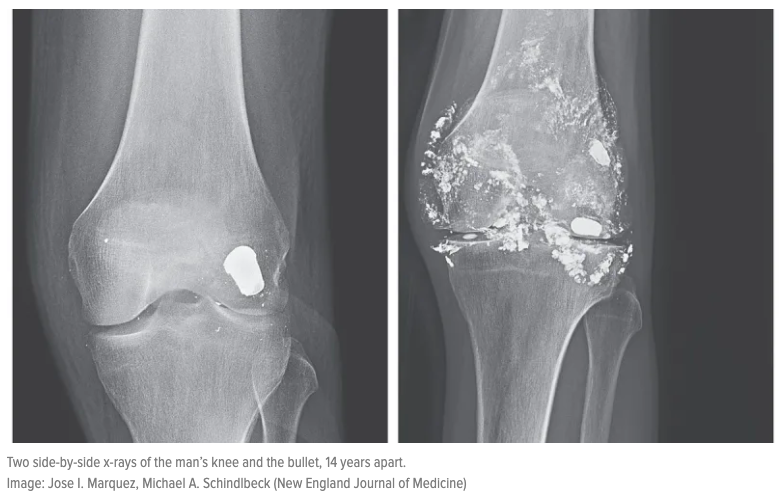

Простреленное плечо

Простреленное плечо 116 фото